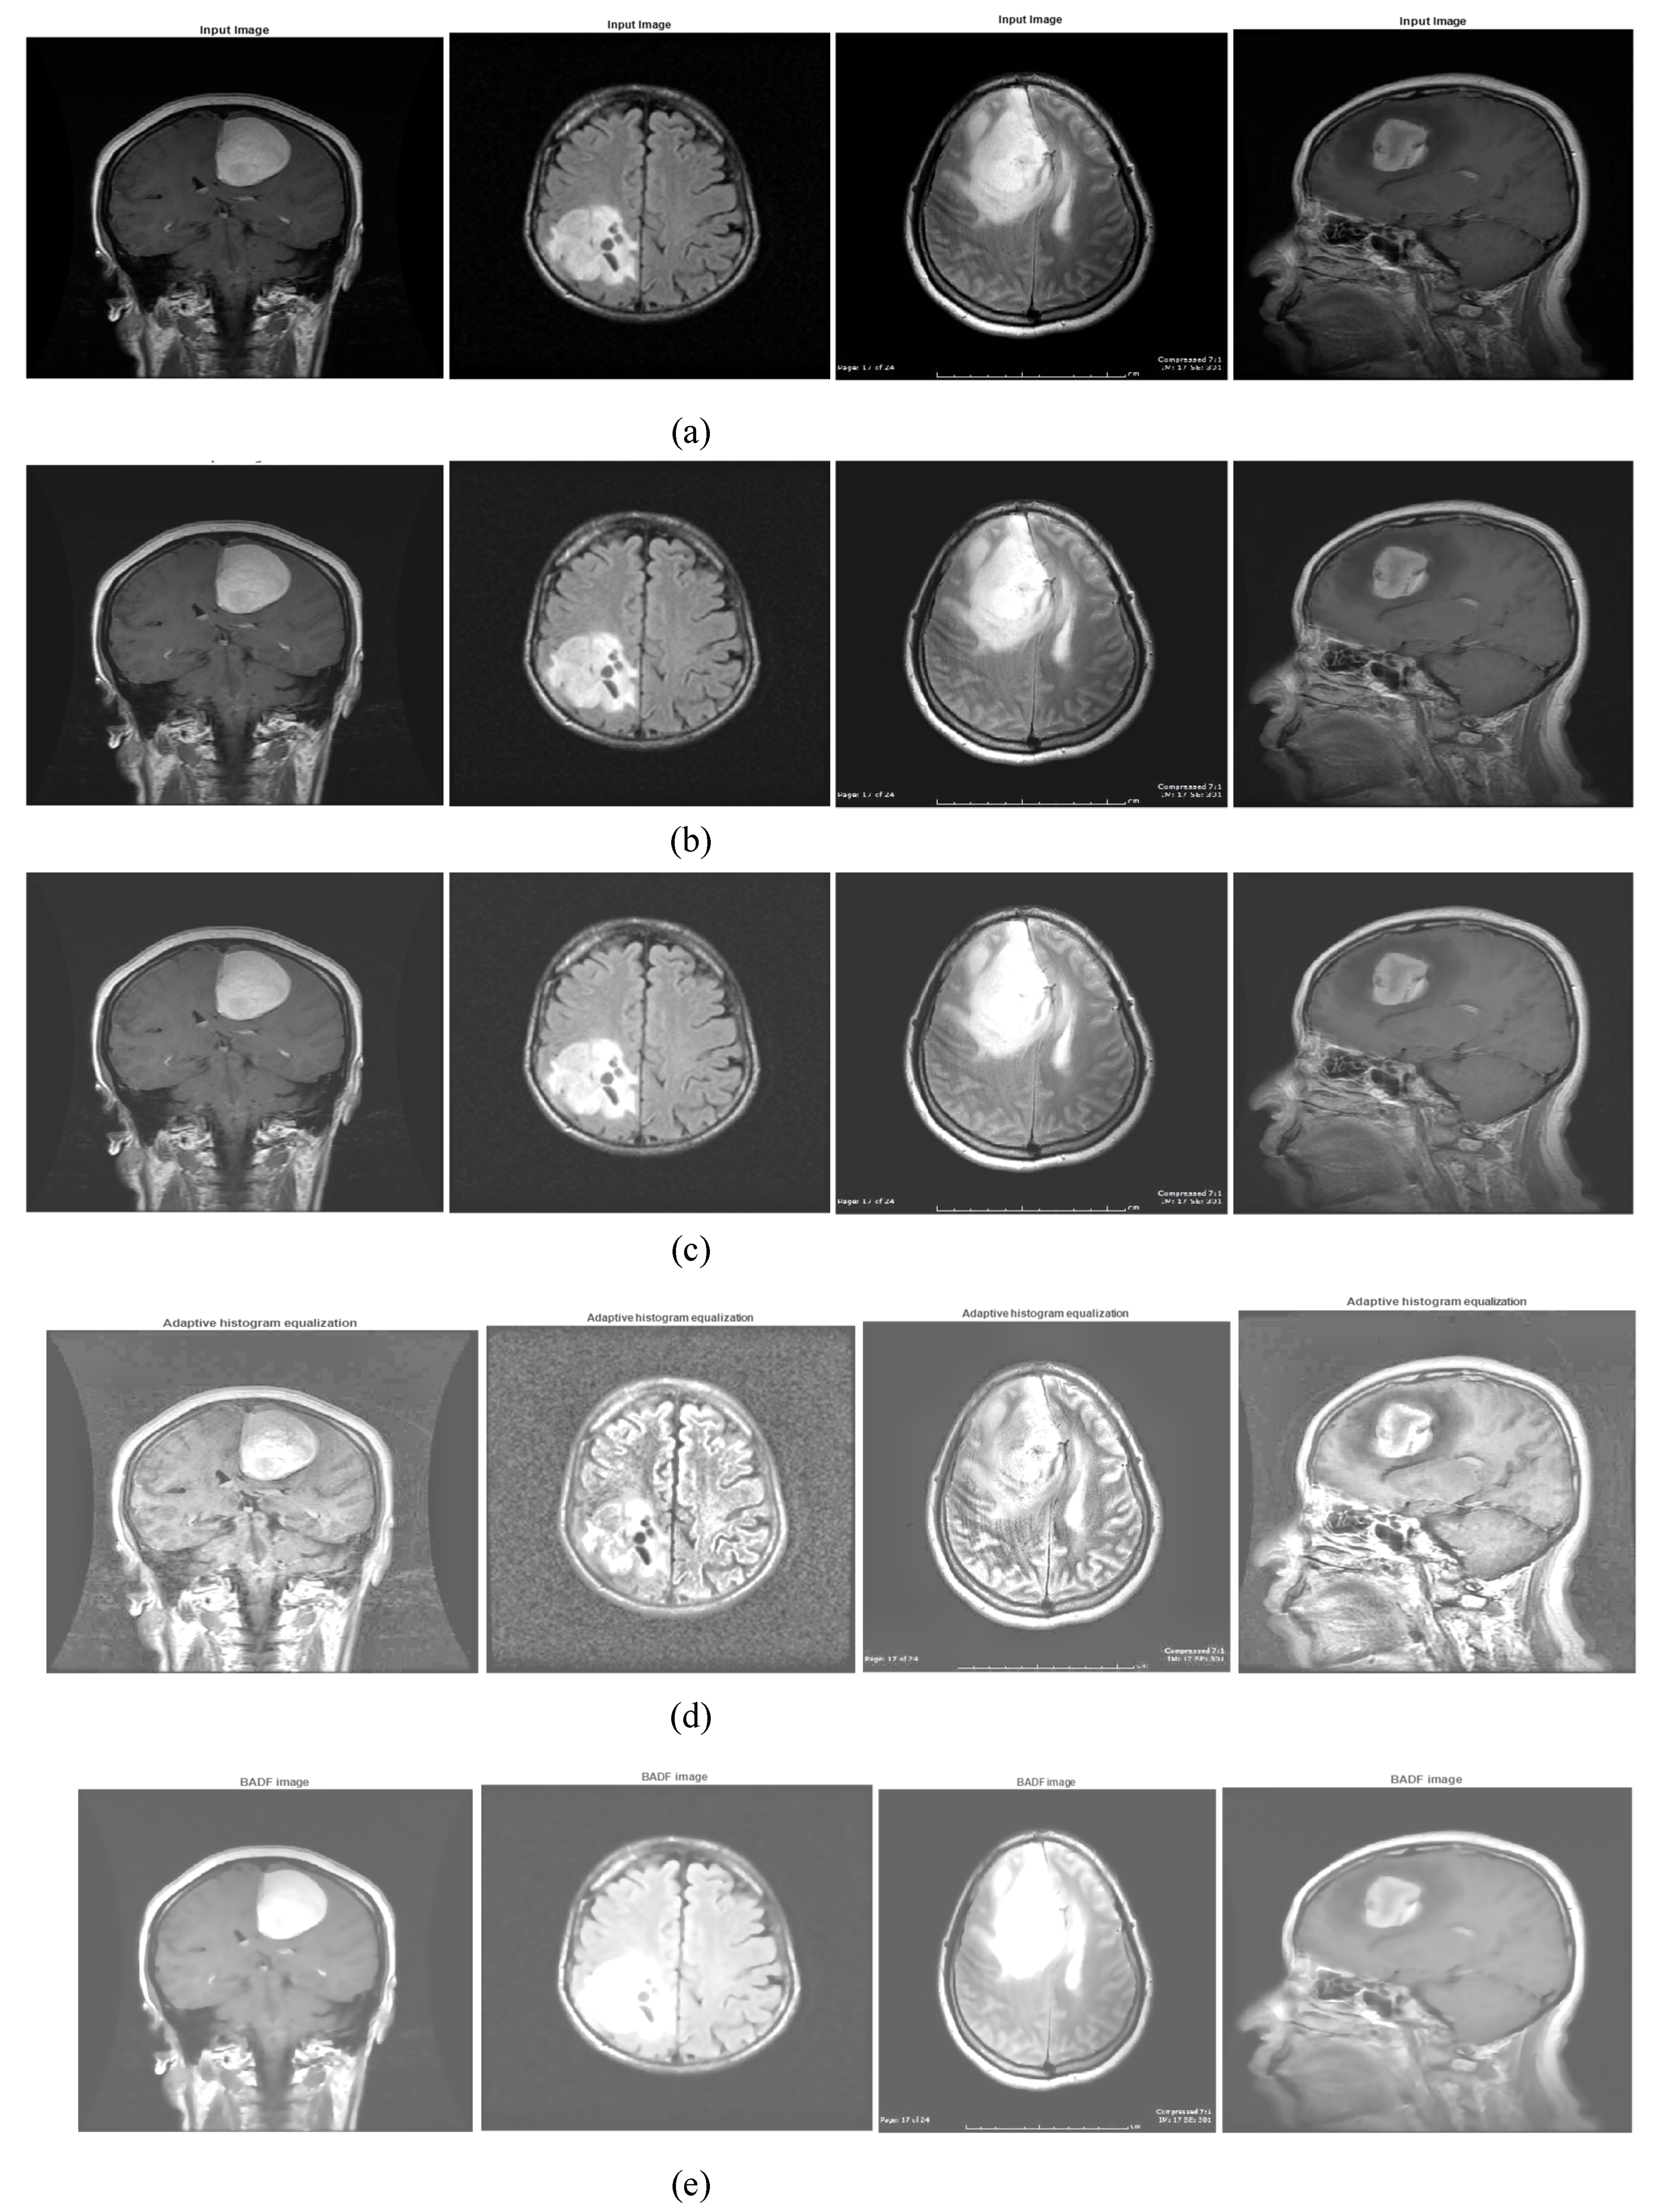

2.2. Preprocessing: Image Enhancement